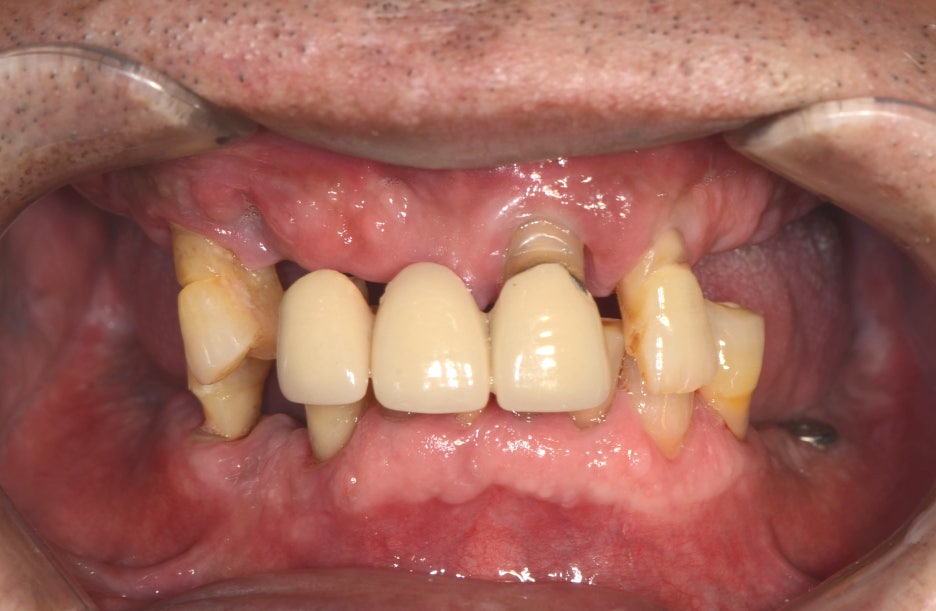

환자분은 잔존한 치아가 얼마 남지 않았지만

그 치아들마저도 치조골 소실로

흔들리는 상태였으며,

전치부만을 사용하여 식사하다 보니

영양소의 섭취도 제대로

이루어지지 않는다고 하셨어요.

나머지 치아들은 모두 발치가 진행되어야 했으며,

하악에 식립 되어 있는 하나의 임플란트에도

염증이 발생되어 있어 함께 제거하기로 했어요.